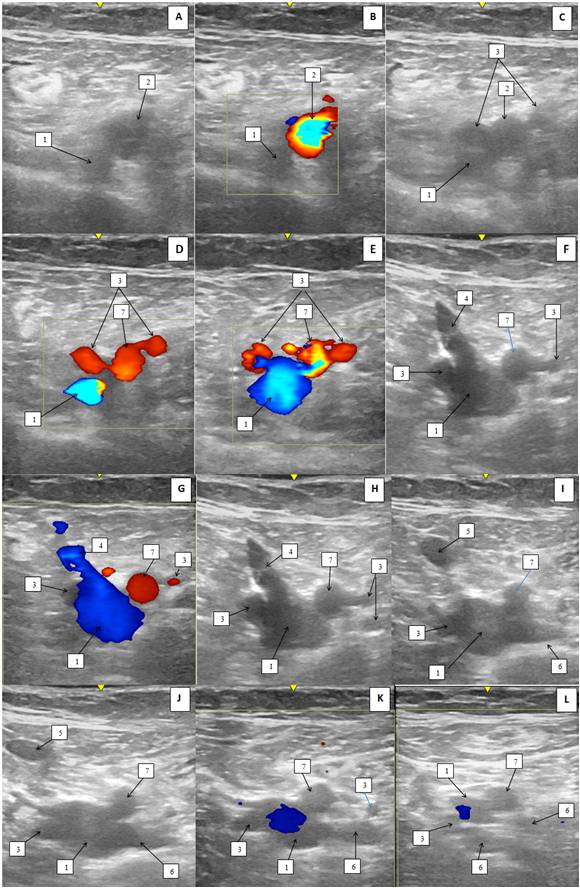

Слева: ГАБ отходит двумя стволами от ОБА с медиальной и латеральной стороны, чуть ниже паховой связки. ОБВ и СФС располагаются между медиальным стволом ГАБ и ПБА. ГВБ представлена двумя стволами, впадающими в БВ с латеральной и задней поверхности (рис. 1, 2).

Рис. 1. Ультразвуковая дуплексная сканограмма сосудов верхней трети бедра слева пациентки К. (двухмерный, серошкальный режим (В-режим) и режим цветового допплеровского картирования; поперечный срез): А–Д — выше уровня сафенофеморального соустья; Е–З — уровень сафенофеморального соустья; И–М — ниже уровня сафенофеморального соустья.

Примечания: 1 — общая бедренная вена, 2 — общая бедренная артерия, 3 — глубокая артерия бедра, 4 — сафенофеморальное соустье, 5 — большая подкожная вена, 6 — глубокая вена бедра, 7 — поверхностная бедренная артерия.